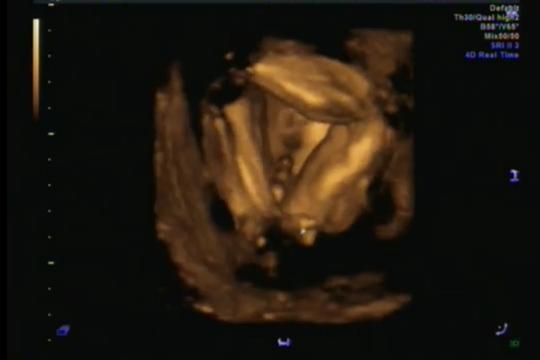

Holka nebo kluk? Matoucí výsledky ultrazvuku ve 26. týdnu

byla jsem na posledním screeningu, kde mi pan doktor řekl, že je to 100% holčička. Na tom by nebylo nic divného, kdyby mi celou dobu všichni netvrdili, že to je kluk, což dle ultrazvuku viz fotky mi připadá jako jasná věc. Fotky jsou z 26tt ze 4D. Moc děkuji za názory 😂

Já u tebe nevím, ona to holka klidně být může, víc by byl ten pytlík dole u zadečku, kdyby to byl kluk myslím... těžko říci...

Ja v tom vidim kluka 😃